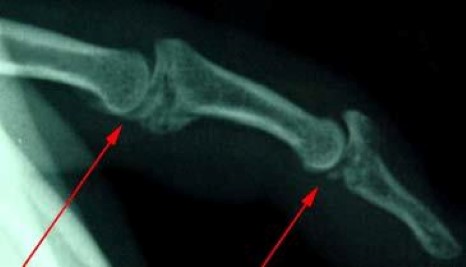

X-ray of fractures within the finger joints

This X-ray shows fractures within the finger joints.